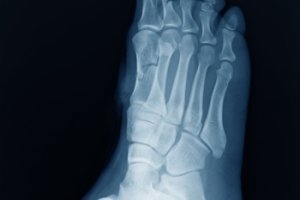

Your podiatrist will diagnose your bunion by doing a thorough examination of your foot. He or she may also conduct an x-ray to determine the cause of the bunion and its severity.

Diagnosis of cuboid syndrome is often difficult, and it is often misdiagnosed. X-rays, MRIs and CT scans often fail to properly show the cuboid subluxation. Although there isn’t a specific test used to diagnose cuboid syndrome, your podiatrist will usually check if pain is felt while pressing firmly on the cuboid bone of your foot.